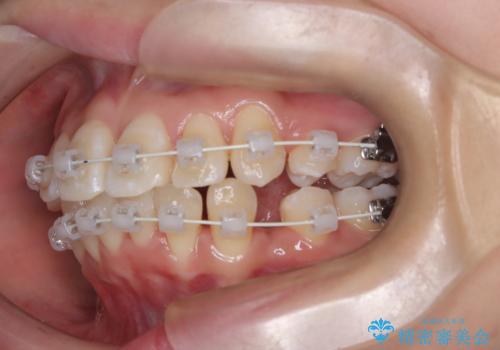

今回の矯正治療では、まず計画通り上下左右の小臼歯4本を抜歯し、八重歯や正中のズレを解消するための十分なスペースを確保しました。装置には、目立ちにくい白いブラケットとワイヤーを使用した審美ワイヤー矯正を採用。

八重歯: 突出していた八重歯を歯列内に誘導し、デコボコを解消しました。

正中のズレ: 歯を左右対称に移動させることで、上下の歯の中心線を正確に合わせ、顔全体のバランスも改善しました。

治療の結果、長年気にされていた八重歯と正中のズレが解消し、機能的にも整った理想的な歯並びを獲得。目立たない装置で治療を完遂し、自信を持って笑える美しい笑顔を手に入れていただけました。